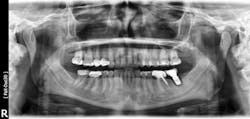

Failures and complications associated with bone augmentation can have a devastating effect on the outcome of dental implant treatment. These complications are classified as either early or late. Early complications include wound dehiscence, membrane and graft exposure, and infection, with the most common complication being wound dehiscence (figures 1a–1c). A strong correlation has been shown between flap tension and wound dehiscence, with wound breakdown occurring in 40% of cases where the flap tension reached 40.1 N as opposed to 10% for flap tensions < 0.1 N.1

Figures 1a–1c: Wound dehiscence occurring after bone augmentation procedures.